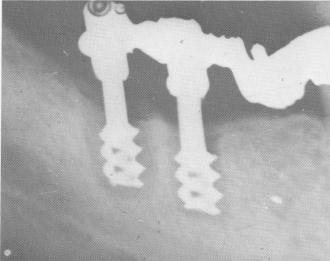

Fig. 14-36. Bone resorption is seen around these two spiral posts because the temporary acrylic splint was worn much too long and loose, thereby loosening the implants.

3 Bone resorption around two spiral posts in mandible